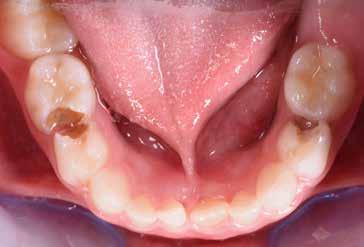

Fig. 125 > Immagine occlusale superiore.

Fig. 18 > Immagine occlusale superiore.

56 > Immagine occlusale superiore.